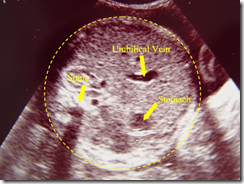

• Evaluasi tali pusat .

• Dilihat jumlah pembuluh darah (bila arteri umbilikalis hanya satu buah maka patut diduga adanya aneuplodi janin, khususnya jika terkait dengan anomali struktur janin.

• Insersi talipusat pada plasenta dan tubuh janin

• Herniasi ekstra abdominal lambung tengah )mid gut) ke talipusat biasanya terjadi pada usia 8 – 12 mingg dan jangan di interpretasikan adanya kelainan dinding perut.janin